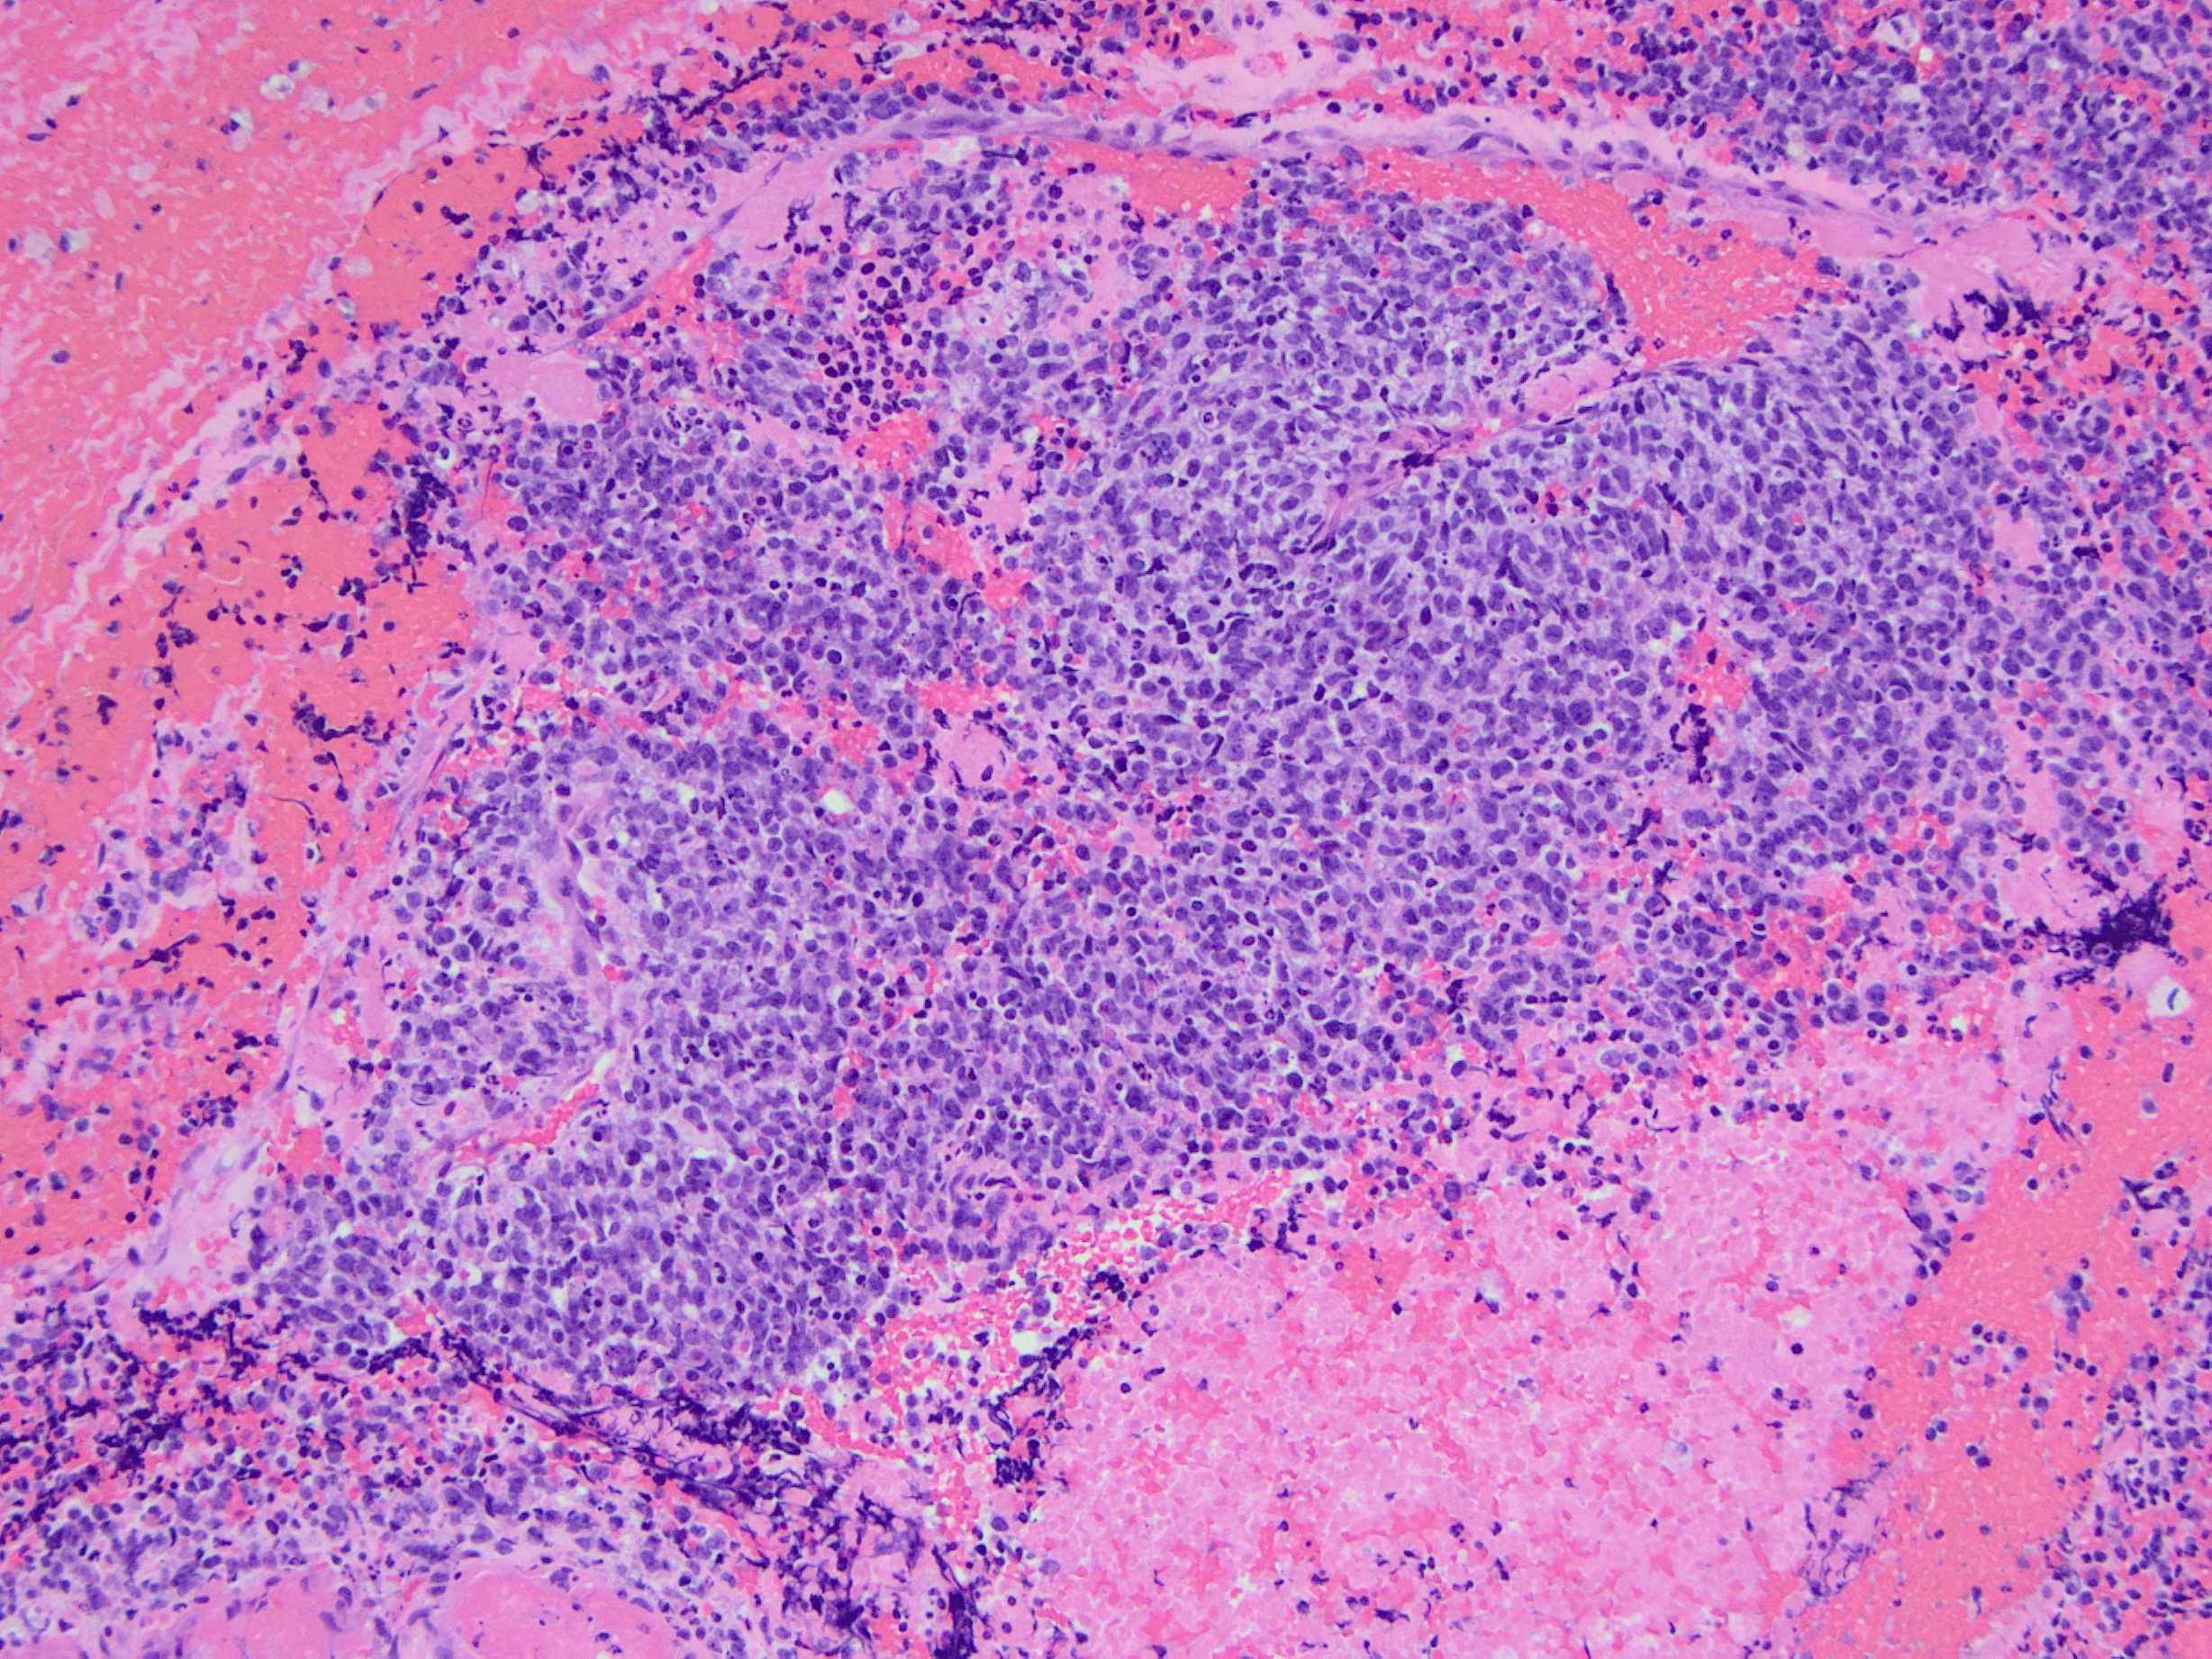

CIC-DUX4 rearranged sarcoma is a small blue round cell tumor resembling Ewing sarcoma. In addition to small blue round cells morphology, CIC rearranged sarcoma may also show focal areas of spindling and epithelioid/rhabdoid phenotype, with frequent myxoid stromal changes. Similar to Ewing sarcoma, it also shows strong cytoplasmic and membranous positivity of CD99. Patient age at presentation ranges from 6 to 70 years (mean age: 32 years). Most of the time it arises in the soft tissue of the trunk and extremities. Overall survival is worse than Ewing sacrcoma.